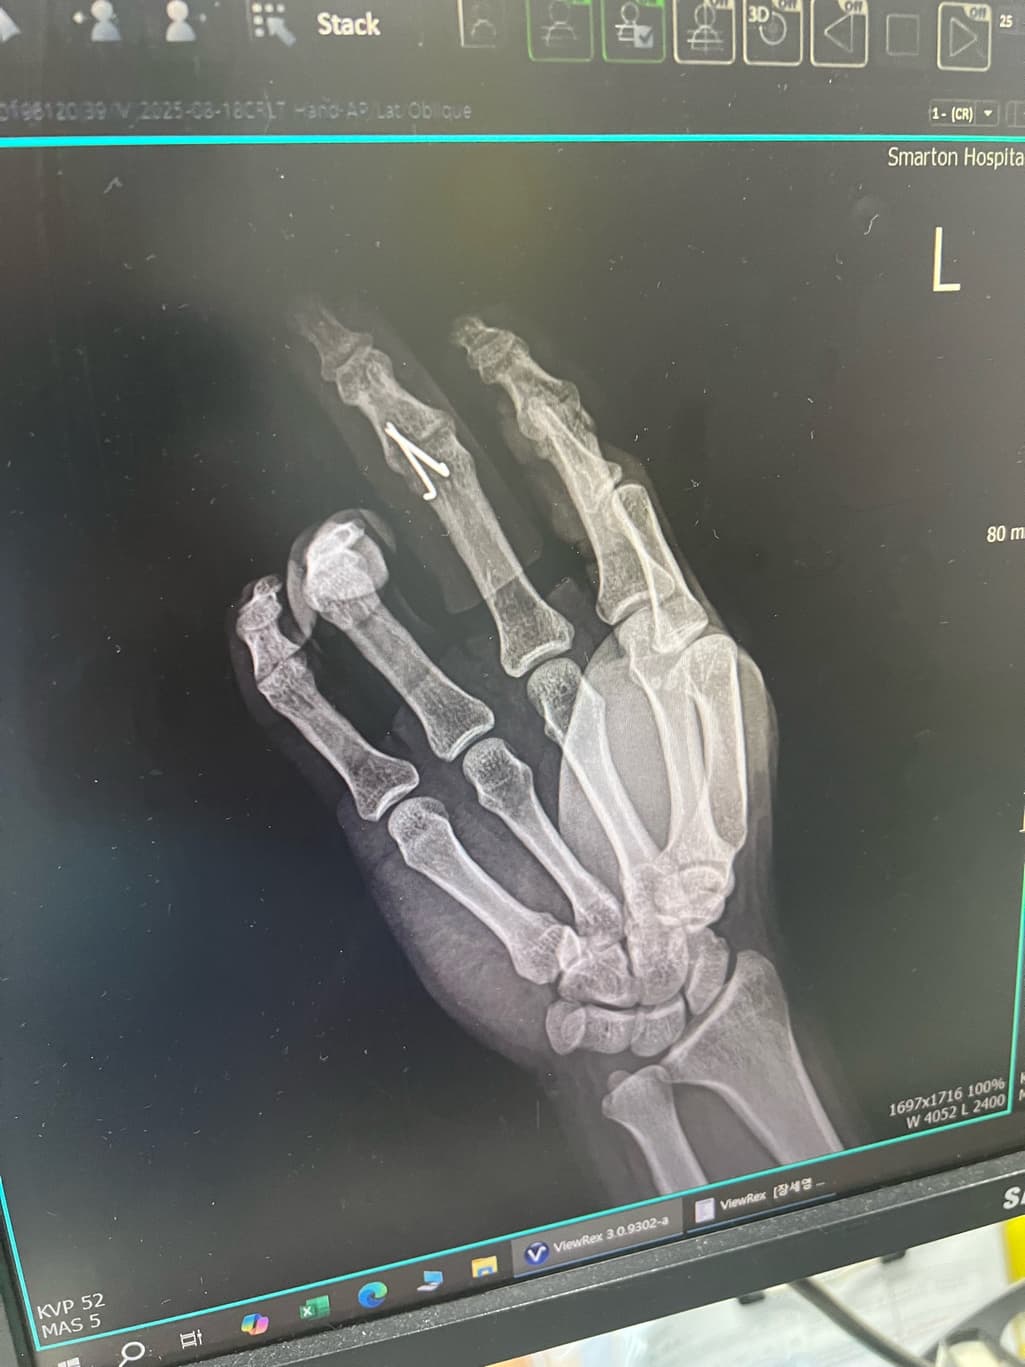

3.골절상태 엑스레이 보시면 몇주정도 후에 핀 뽑아도 되는지 판단부탁드립니다.

올리신 사진만으로 구체적인 판단을 내리기에는 근거가 충분하지 않습니다만, 손가락 부위 골절이라면 4주 만에 핀을 뽑는 경우도 있긴 하겠습니다. 그보다 자세히 어떻다고 이야기를 드리기는 조심스럽습니다.